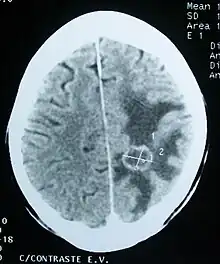

Imaging

Medical imaging plays a central role in the diagnosis of brain tumors. Early imaging methods – invasive and sometimes dangerous – such as pneumoencephalography and cerebral angiography have been abandoned in favor of non-invasive, high-resolution techniques, especially magnetic resonance imaging (MRI) and computed tomography (CT) scans, though MRI is typically the reference standard used.[37] Neoplasms will often show as differently colored masses (also referred to as processes) in CT or MRI results.

- Benign brain tumors often show up as hypodense (darker than brain tissue) mass lesions on CT scans. On MRI, they appear either hypodense or isointense (same intensity as brain tissue) on T1-weighted scans, or hyperintense (brighter than brain tissue) on T2-weighted MRI, although the appearance is variable.

- Contrast agent uptake, sometimes in characteristic patterns, can be demonstrated on either CT or MRI scans in most malignant primary and metastatic brain tumors.

- Pressure areas where the brain tissue has been compressed by a tumor also appear hyperintense on T2-weighted scans and might indicate the presence a diffuse neoplasm due to an unclear outline. Swelling around the tumor known as peritumoral edema can also show a similar result.